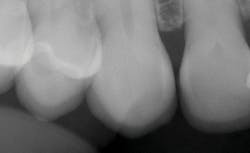

The new veneers are shown from the facial view in Figure 14 and incisal view in Figure 15. In the radiograph in Figure 16, the thin veneers can be seen in place. This case illustrated to me that thin veneers bonded to enamel have the potential to last for many years.

Figure 16: Radiographic view of the veneers in place